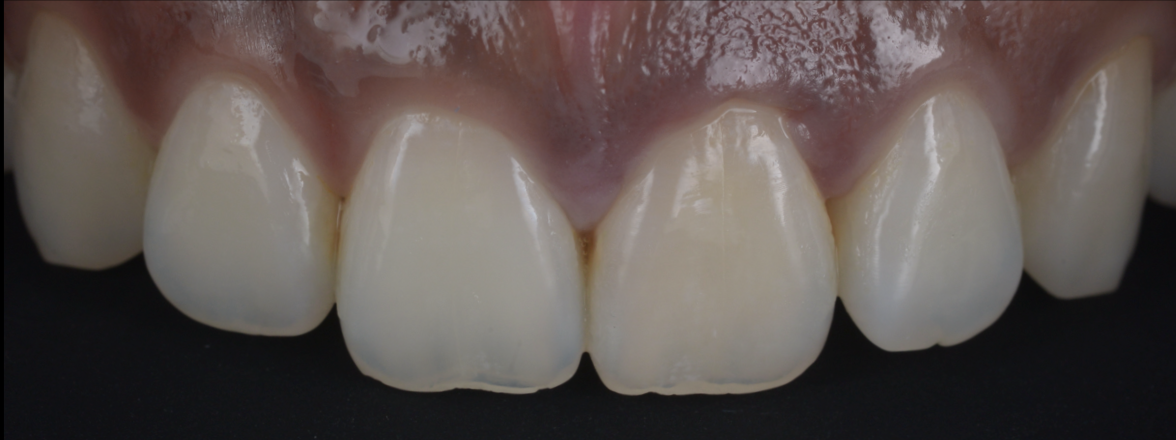

上唇の腫脹を認め、CT検査にて根尖部に嚢胞様透過像を認めた。左上の前歯が不自然に大きく噛み合わせが強くなっていたことがフレアアップの一因と考える。精密根管治療を行い、感染経路を遮断したのち歯根端切除術にて嚢胞を摘出した。

治療後